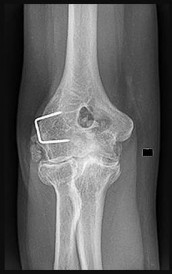

Question 8

A 30-year-old male presents with a slow-growing, deep-seated, painful soft tissue mass in his left foot near the ankle joint. Imaging reveals a heterogeneous mass with stippled calcifications. Biopsy demonstrates a biphasic pattern consisting of spindle cells and epithelial cells. Which of the following cytogenetic abnormalities is classically associated with this tumor?

Explanation

The clinical, radiographic, and histologic descriptions are classic for synovial sarcoma. Synovial sarcoma is characterized by the specific chromosomal translocation t(X;18)(p11;q11), which results in the SYT-SSX fusion gene. This molecular marker is highly sensitive and specific for confirming the diagnosis.